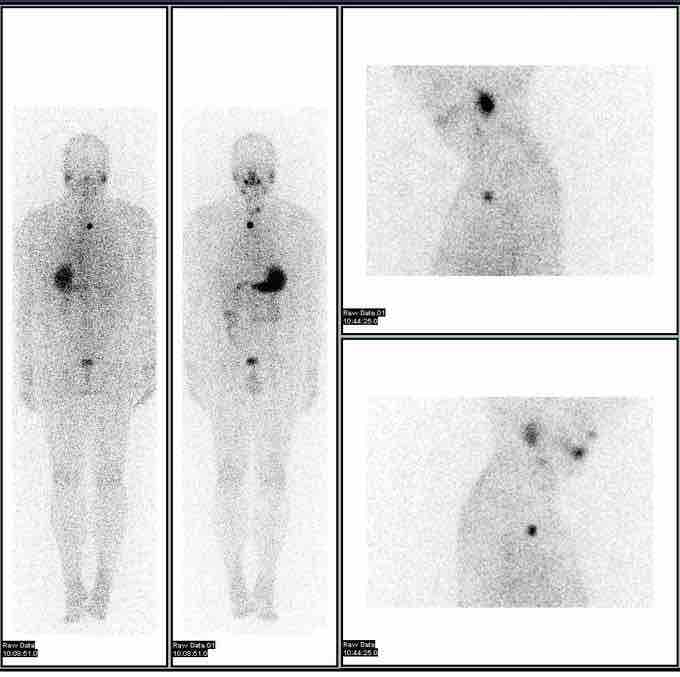

Iodine-123 whole-body scan

These images are scans used in the evaluation of thyroid cancer using the isotope iodine-123.